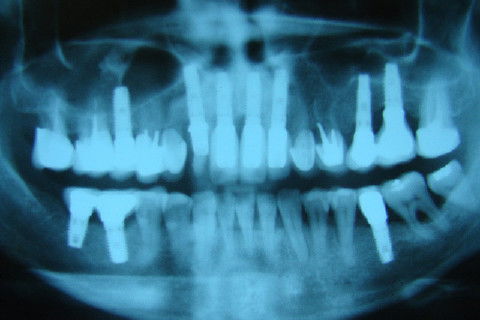

Radiografia inicial

Radiografia panoramica após o termino do tratamento